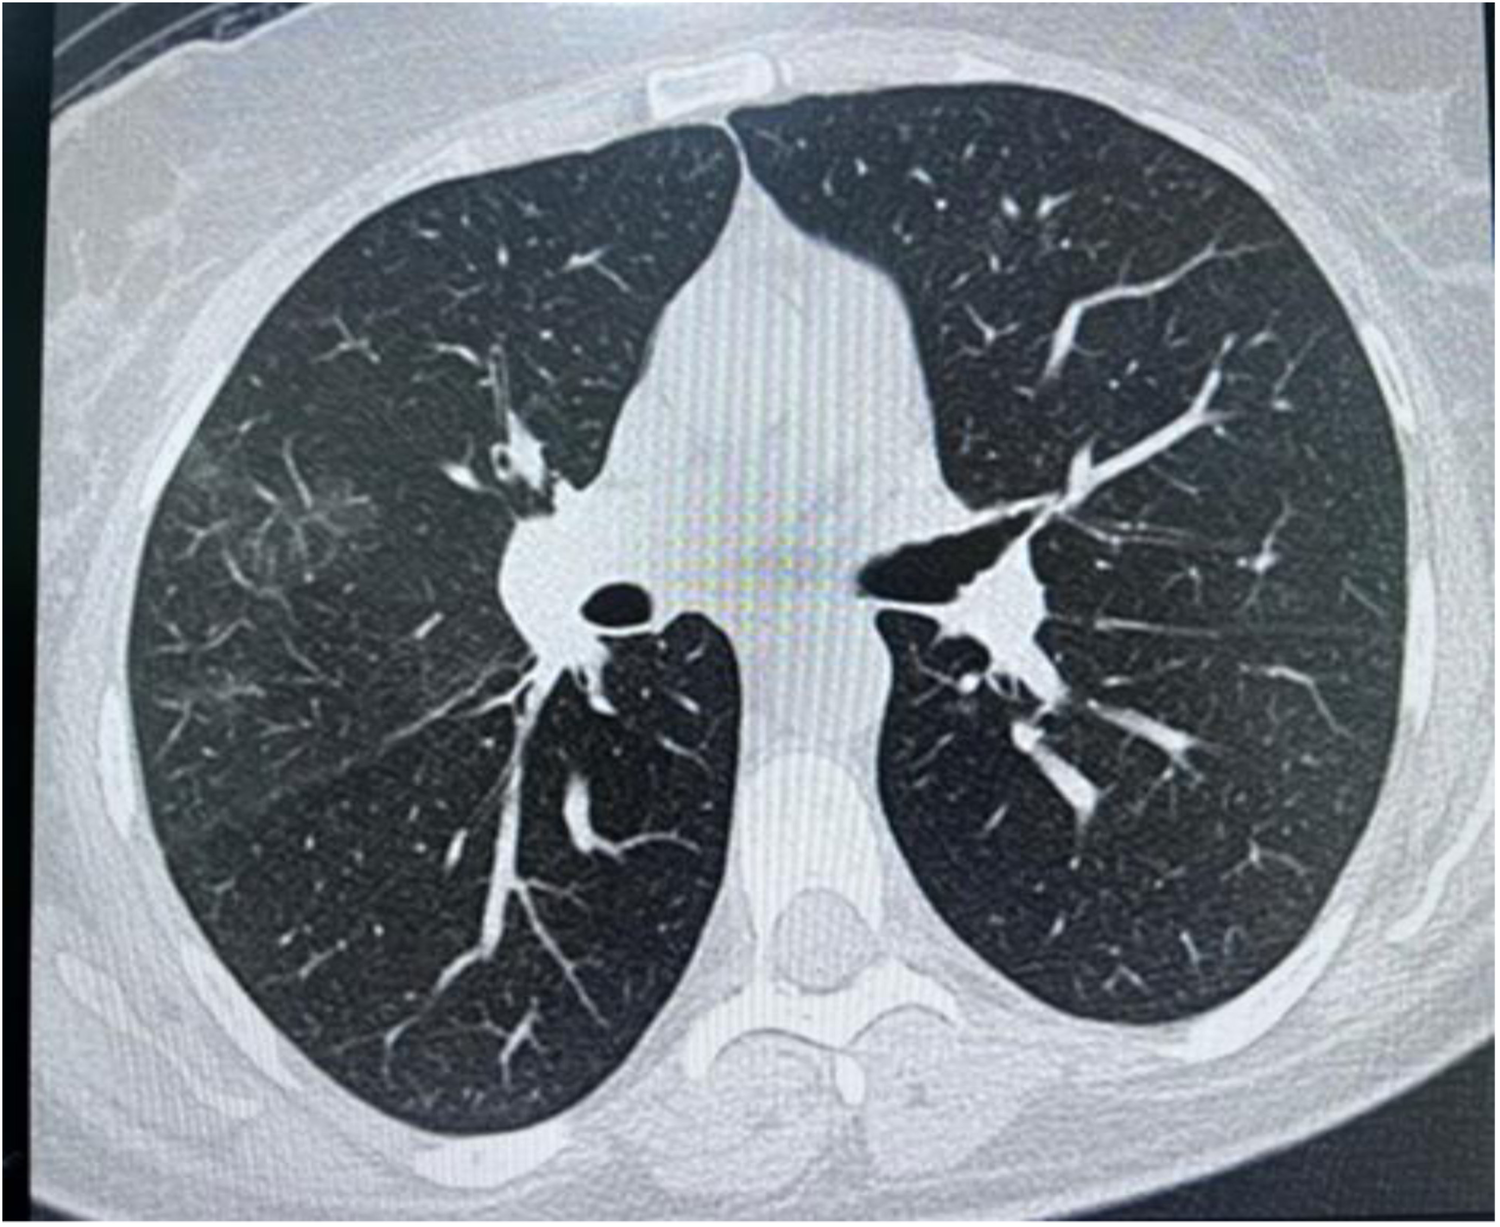

High-resolution computed tomography (HRCT) chest showed a few peripheral and central faint patchy areas of ground glass densities in the lower segment of the right upper lobe, with no signs of lung masses, consolidation, or cavitation (Figure 3). There was ground glass densities in the right upper lobe, possibly indicative of an inflammatory or infectious process. Furthermore, there was no mediastinal lymph node enlargement or pneumothorax.

Figure 3

High resolution computed tomography (HRCT) chest showing peripheral and central faint patchy areas of ground glass densities within the lower segment of right upper lobe.

With a background history of asthma, eosinophilia, chest involvement in HRCT, and the presence of neuropathy, diagnosis of EGPA was considered, and further investigations were conducted. ANCA was negative. Urine analysis was negative for blood and red RBCs casts (Table 2).